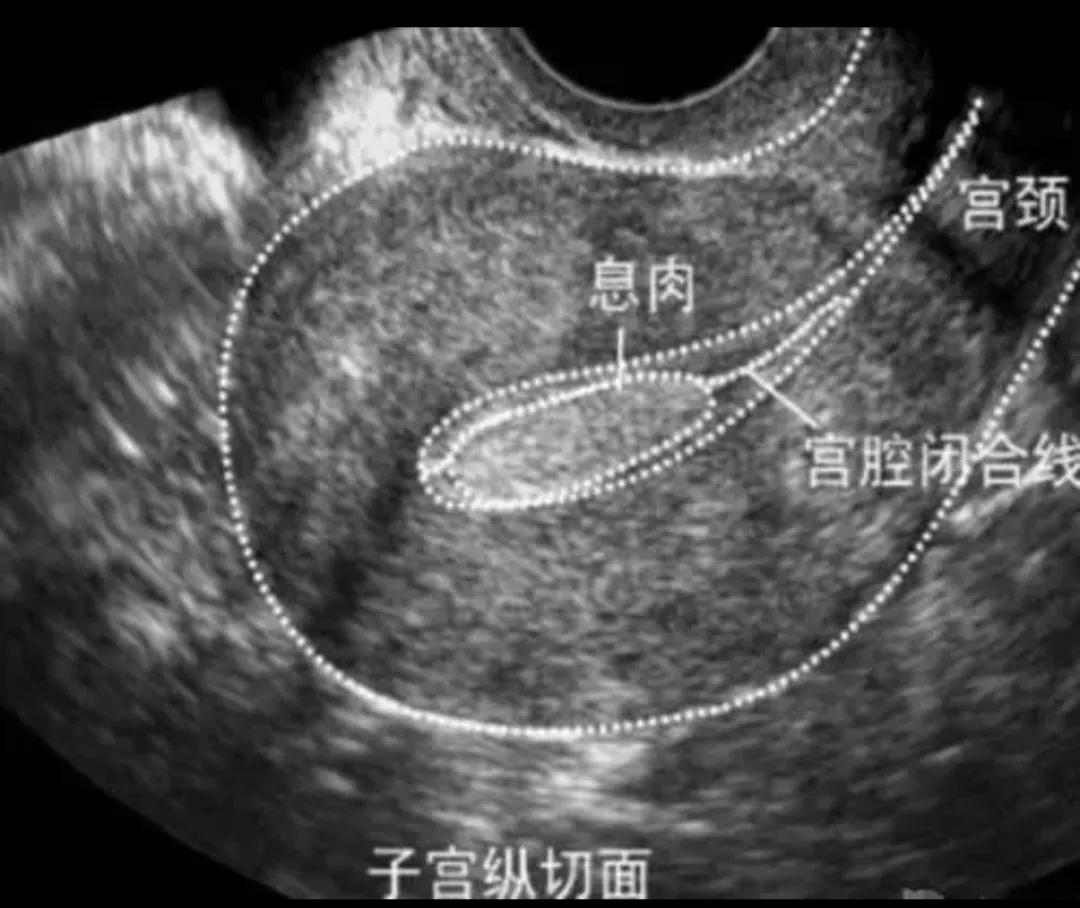

子宫息肉

子宫息肉是由于子宫局部内膜过度生长并向宫腔延伸的增生物。子宫息肉最常见的就是子宫内膜息肉,它是子宫局部的内膜过度生长所导致的。

子宫内膜息肉可以发生在女性的各个年龄段,它的恶变程度不高,但是在绝经后人群中会发生一定的癌变。

子宫息肉的发现可以通过妇科检查,经阴道超声检查等可以发现的,可以在宫腔镜下进行切除。